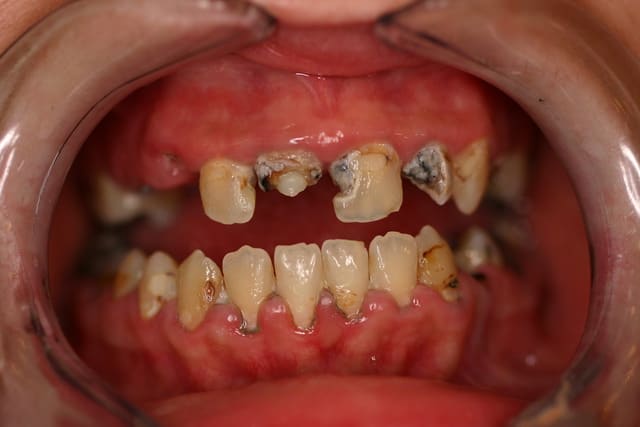

Joli aussi ça non ???

Pp ;-)

Non hélas patiente de 28 ans...

Si c était Pp , vu son grand âge, ce serait moins grave

Néanmoins patiente traitée ...

Oui bien sûr placé sous 48 h

Les piliers seront retirés sur les molaires par la suite

Pp